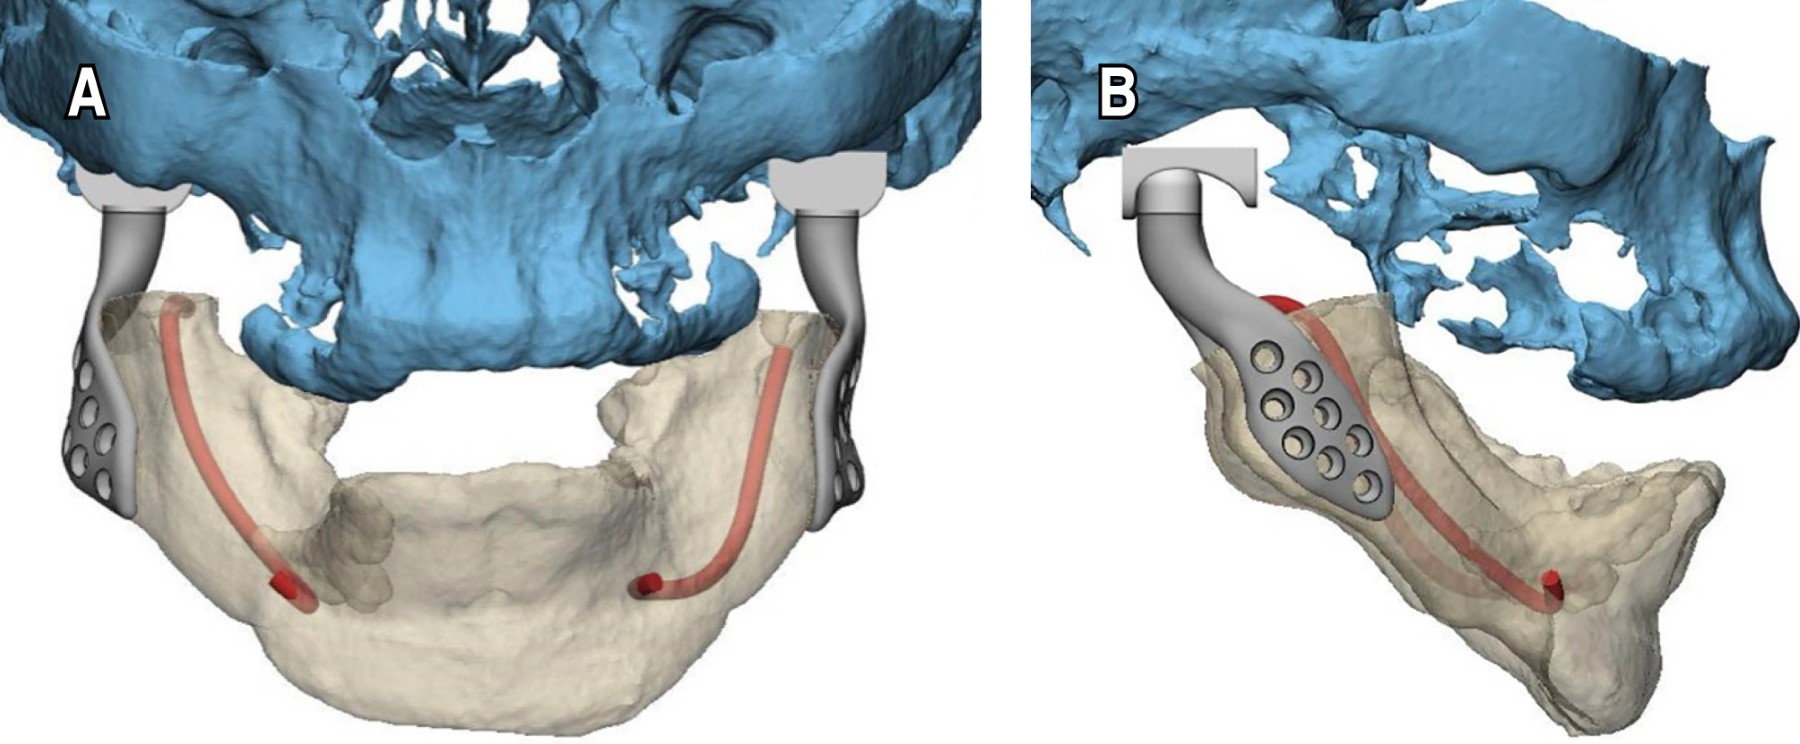

Durante la planificación quirúrgica, se analizó la opción de una prótesis personalizada de articulación temporomandibular, ya que, debido al gran avance del caso, no era posible utilizar una prótesis estándar (Figura 2). Una de las dificultades del caso fue que la paciente presentaba edéntula bimaxilar, lo que dificultaba la planificación de la relación maxilomandibular y la fijación de las prótesis, al no existir una referencia oclusal (Figura 3). La planificación se basó en los exámenes de imagen. Su fijación se realizó teniendo en cuenta la anatomía mandibular y la perfecta adaptación de la prótesis personalizada.

Figura 4